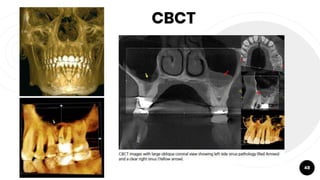

CBCT

48